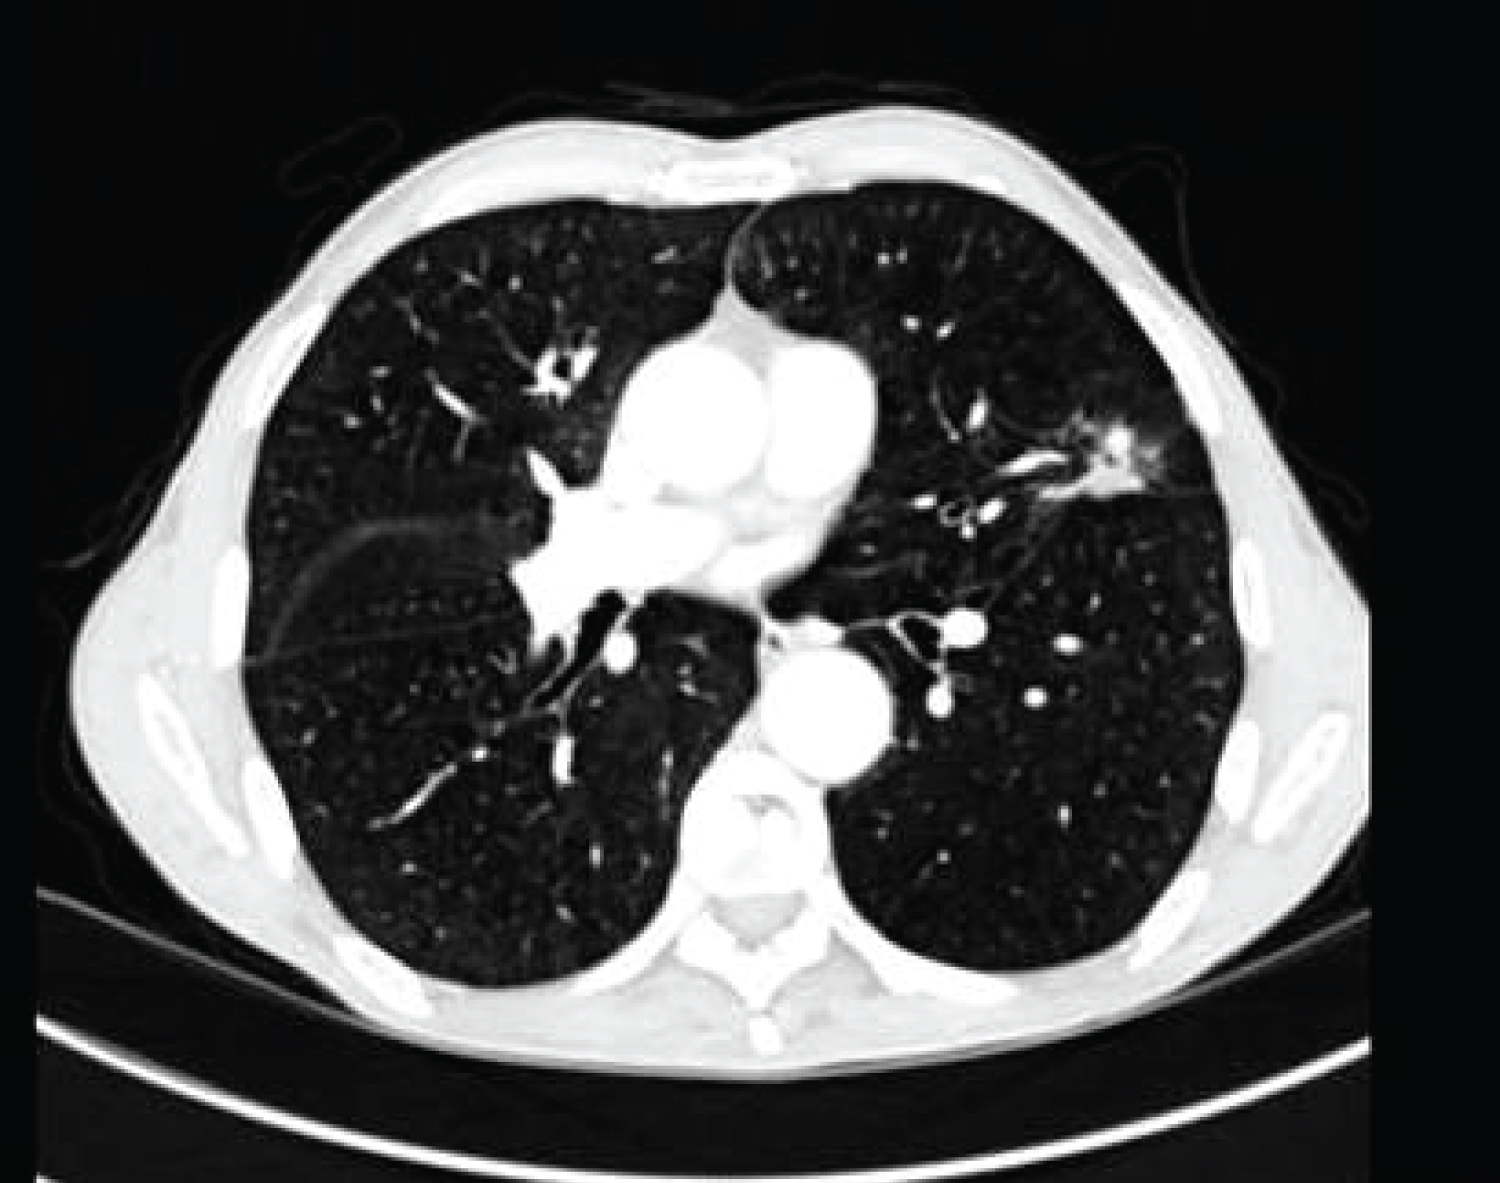

A 63-year-old man, an active smoker 50-pack-year with a history of chronic obstructive lung disease presented with one year worsening dyspnea. Chest X-ray showed opacity of left upper lobe. Bronchoscopic findings were unremarkable. Lung function testing registered obstructive ventilator defect. Chest computed tomography scan showed a highly suspected perifissural nodule of 23 mm in the left-upper lobe. The nodule was irregular with spiculated contours and a central necrosis (Figure 1). The patient underwent a left-upper lobectomy. Gross examination showed a tan-white cystic nodule measuring 2 cm in greatest dimension filled with gelatinous materiel on the cut surface. Microscopic examination revealed an invasive tumor arranged in acinis and papillary structures which are dissected by pool of extracellular mucin distending alveolar spaces and destructing their walls (Figure 2). They were covered by a pseudostratified columnar epithelium consisted of well-differentiated tall mucinous columnar cells with mild to moderate cytologic atypia (Figure 3). The fibro-inflammatory stroma contains multiple multinucleated giant cells phagocyting the mucin. Immunohistochemically, the tumors cells showed diffuse positive staining for CK7, CDX2, MUC2, MUC5 and focal staining for CK20 and TTF-1. These findings were consistent with the diagnosis of primary pulmonary colloid adenocarcinoma. The patient had an uneventful postoperative course. The patient is asymptomatic for two years after the operation.

Figure 1: Chest computed tomography showing an irregular speculated mass in the left-upper lobe. View Figure 1